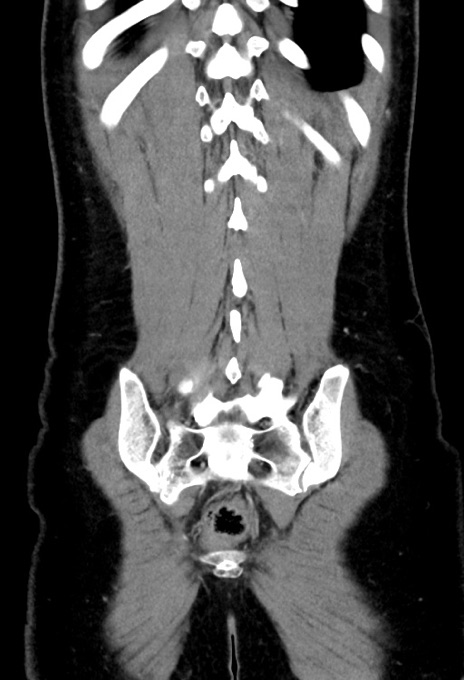

横断像

【症例】20歳代女性

【主訴】嘔吐、下腹部痛

【現病歴】昨日夕食後に嘔吐し下腹部痛が出現。本日になっても嘔吐持続し改善しないため来院。

【身体所見】意識清明、BT 37.2℃、BP 108/67mmHg、腹部:平坦、やや硬、下腹部正中から右にかけて圧痛あり、反跳痛軽度あり、tapping pain(+)。

【データ】WBC 13600、CRP 14.94